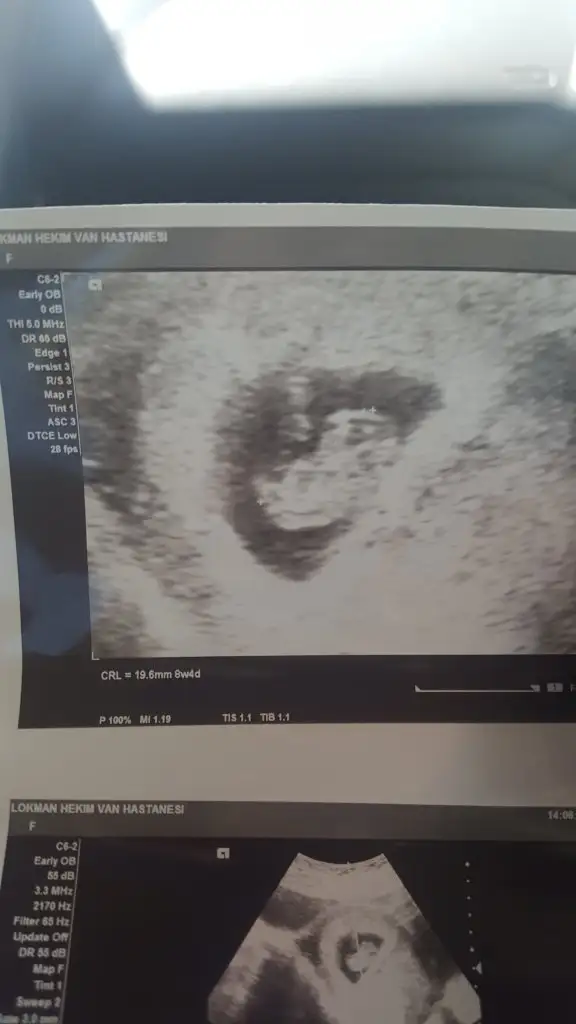

Biliyorum belki çok erken ama merak işte 9 haftadayım herhangi bir tahmin yapabilir misiniz

Haklısın cuma kontrolü varmış ama cinsiyet belli olur heralde 13+ oldu çünküBuna ne tahmin etsem %50 yarı yarıya tahmin olur çünkü çok erken nu bu haftalarda iki tarafa benzer şimdilik erkek yönünde tutmayabilir yuzde verdim

En iyi 11 12 13 şimdilik erkek kese konumuAnlayanlar bunada bir yorum yapabilir misiniz acaba